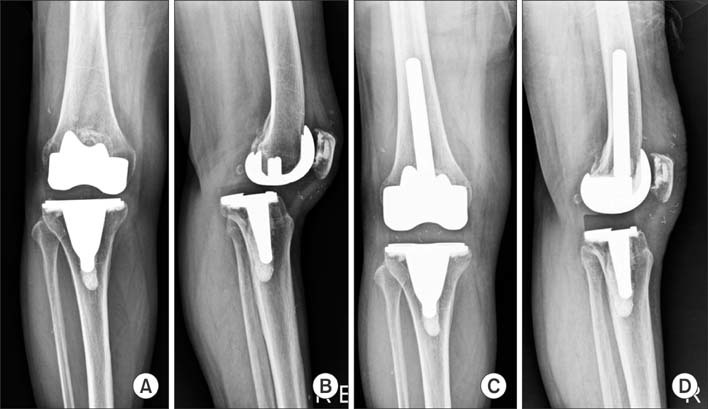

Indications for the use of this prosthesis?

the patient depicted had instability following CR knee and PCL rupture

Indications for the following prosthesis

Constrained hinge with rotating platform

Why was this prosthesis choosen?

Tumour Prosthesis